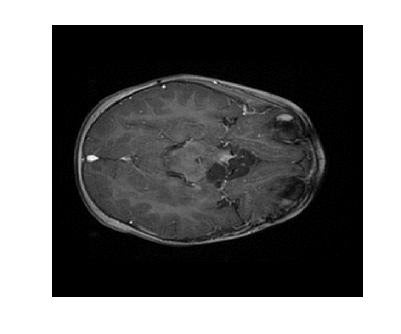

Due to its wide use in image processing, we consider the use of gradient sparsification with LACS-MRI. We show below that it is possible to produce image reconstructions with significantly higher Reconstruction SNR using gradient sparsification. We have repeated some of the simulations from above for different compression levels, , using the gradient transform to sparsify instead of the wavelet transform. We will refer to this as ”LACS-MRI with gradient sparsity.” We compared the performance of each sparsification method at each compression level using LACS-MRI and then compared this to the L1-W method. Again, we use a reference image and a follow-up image that we hope to recover as in Figure 8. We consider here only the phantom image, as it serves as a prime candidate for gradient sparsification, and is small enough that evaluation of all PDFs is computationally feasible.

We re-ran simulations for cases 7, 8, 17, and 18 on the phantom. Over 30 trials, using the gradient on the phantom image resulted in much higher RSNR for every single case. Cases 7 and 17 both also outperformed cases 8 and 18 every time by about 13%. These cases both used the variable density sampling method and LACS-MRI. Figure 9 shows the reconstruction from Case 17. The recovered image using LACS-MRI with wavelet sparsity is more pixelated near the tumor while LACS-MRI with gradient sparsity produced an almost perfect reconstruction. Figure 11 shows the great disparity between the two sparsifying methods. On average, the four phantom reconstructions using the gradient only needed to sample about 6% of the data to achieve the same RSNR that the reconstructions using the wavelets did at 21% sampling.

We also compare the LACS-MRI gradient method to the Cases 9 and 10 which use -minimization with wavelet sparsity. Clearly, the L1-W method recovered the phantom image very poorly, as shown in Figure 10 and Figure 11 (b). The image is blurry even when 18% of the available data was sampled. The RSNR of L1-W is worse than both the RSNR achieved by LACS-MRI with wavelet sparsity and LACS-MRI with gradient sparsity.